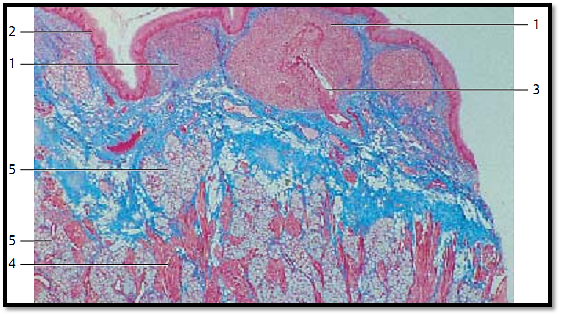

Lingual Tonsil

This vertical section through the root of the tongue shows the lingual follicles 1. The top part of the figure reveals the multilayered nonkeratinizing squamous epithelium of the root of the tongue 2 and the underlying lymphoreticular tissue 1 . Striate d muscle fibers of the lingual musculature 4 are visible in the lower half of the image. The muscle cells are interspersed with the lobules of the posterior lingual mucous glands 5 . The connective tissue is stained blue.

1 Lymphoreticular tissue

2 Epithelium of the root of the tongue

3Crypt

4 Tongue musculature

5 Mucous glands

Stain: azan; magnification: × 12